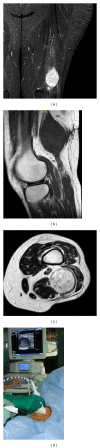

In the management of bone and soft tissue tumors, accurate diagnosis, using a combination of clinical, radiographic, and histological data, is critical to optimize outcome. On occasion, diagnosis can be made by careful history, physical examination, and images alone. However, the ultimate diagnosis usually depends on histologic analysis by an experienced pathologist. Biopsy is a very important and complex surgery in the staging process. It must be done carefully, so as not to adversely affect the outcome. Technical considerations include proper location and orientation of the biopsy incision and meticulous hemostasis. It is necessary to obtain tissue for a histological diagnosis without spreading the tumor and so compromise the treatment. Furthermore, the surgeon does not open compartmental barriers, anatomic planes, joint space, and tissue area around neurovascular bundles. Nevertheless, avoid producing a hematoma. Biopsy should be carefully planned according to the site and definitive surgery and should be performed by an orthopedic surgeon with an experience in musculoskeletal oncology who will perform the definitive surgery. Improperly done, it can complicate patient care and sometimes even eliminate treatment options. Different biopsy techniques are suitable: fine-needle aspiration, core-needle biopsy, and incisional biopsy. The choice of biopsy depends on the size, the location of the lesion, and the experience of the pathologist.